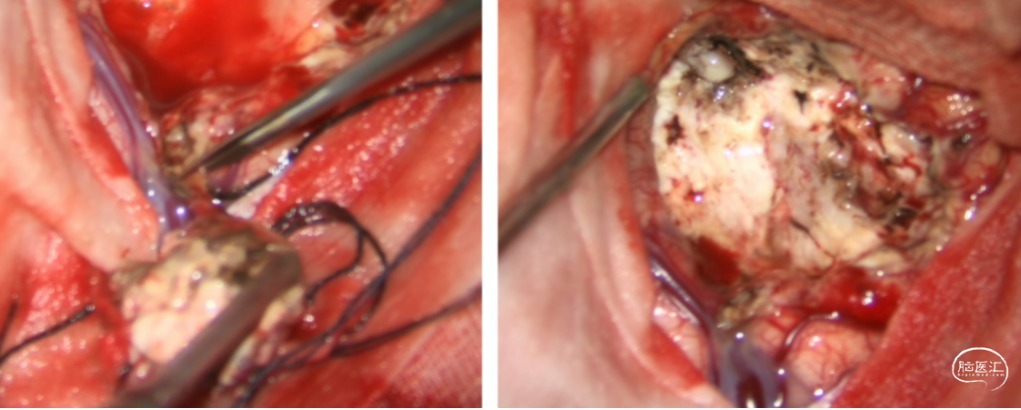

分离:沿边界分离畸形团,离断供血动脉;

切断:最后切断引流静脉,术区止血满意;